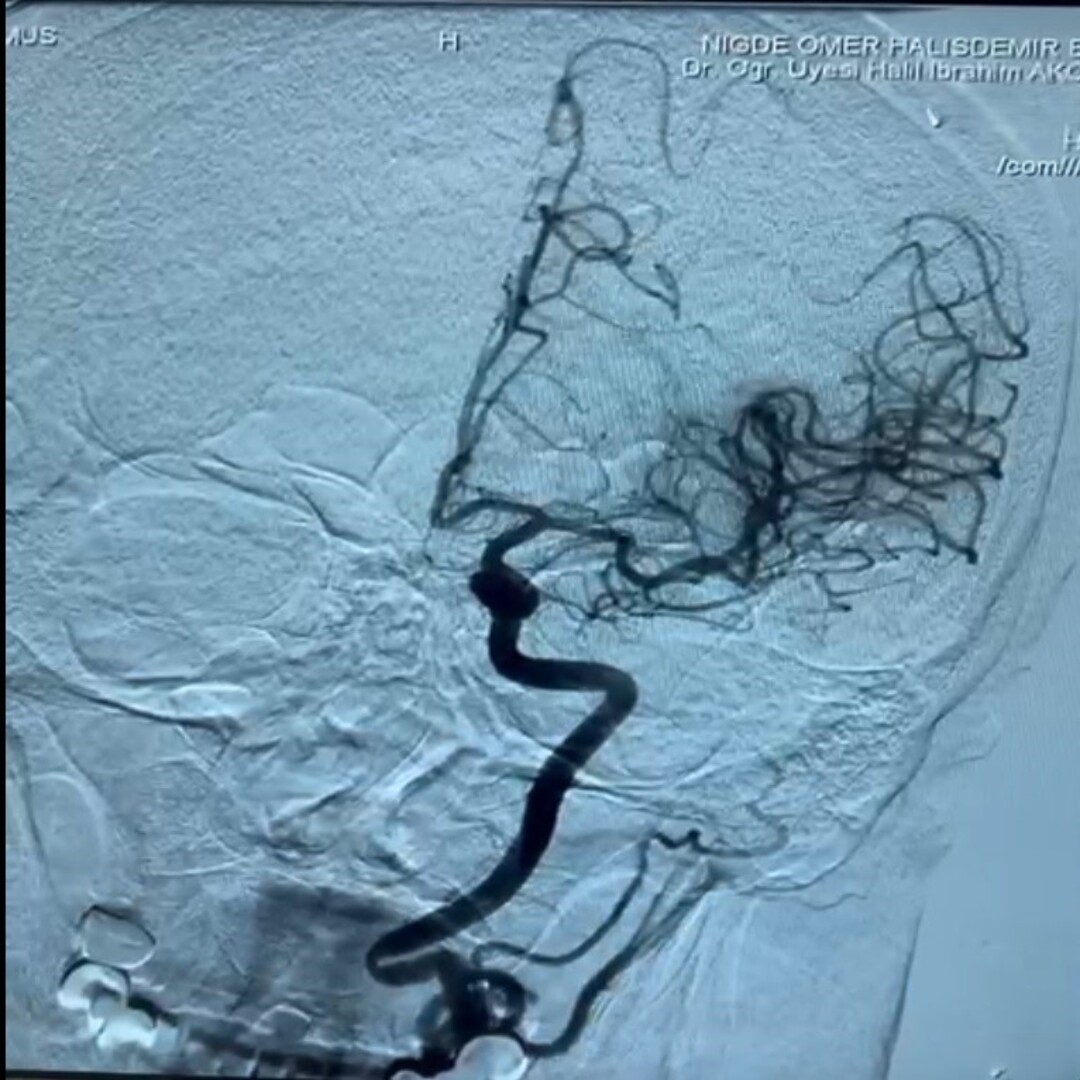

İnmenin, beyin damarlarında tıkanma ya da kanama sonucu felç ve ölüme neden olan ciddi bir sağlık sorunu olduğunu vurgulayan Dr. Akçay, dünya genelinde erişkin yaş grubunda ölümlerin ikinci en sık nedeninin inme olduğunu, nörolojik engelliliğin ise en sık nedeninin yine inme olduğunu ifade etti. Dr. Akça; "İnmelerin yüzde 80’i damar tıkanıklığına bağlı gelişiyor. Diyabet, obezite ve yaşam süresinin uzaması gibi faktörler inme riskini etkiliyor. İnme merkezimizde, hastalara erken dönemde kateter anjiyografi yöntemi ile pıhtı çıkarma ve damardan kan sulandırıcı tedavileri 7/24 uygulanmaktadır. Bu nedenle, tedavide zaman kaybını önlemek amacıyla 112 sağlık hizmetleri, hastane acil servisi ve inme merkezi ekibimiz koordineli bir şekilde çalışmaktadır." dedi.